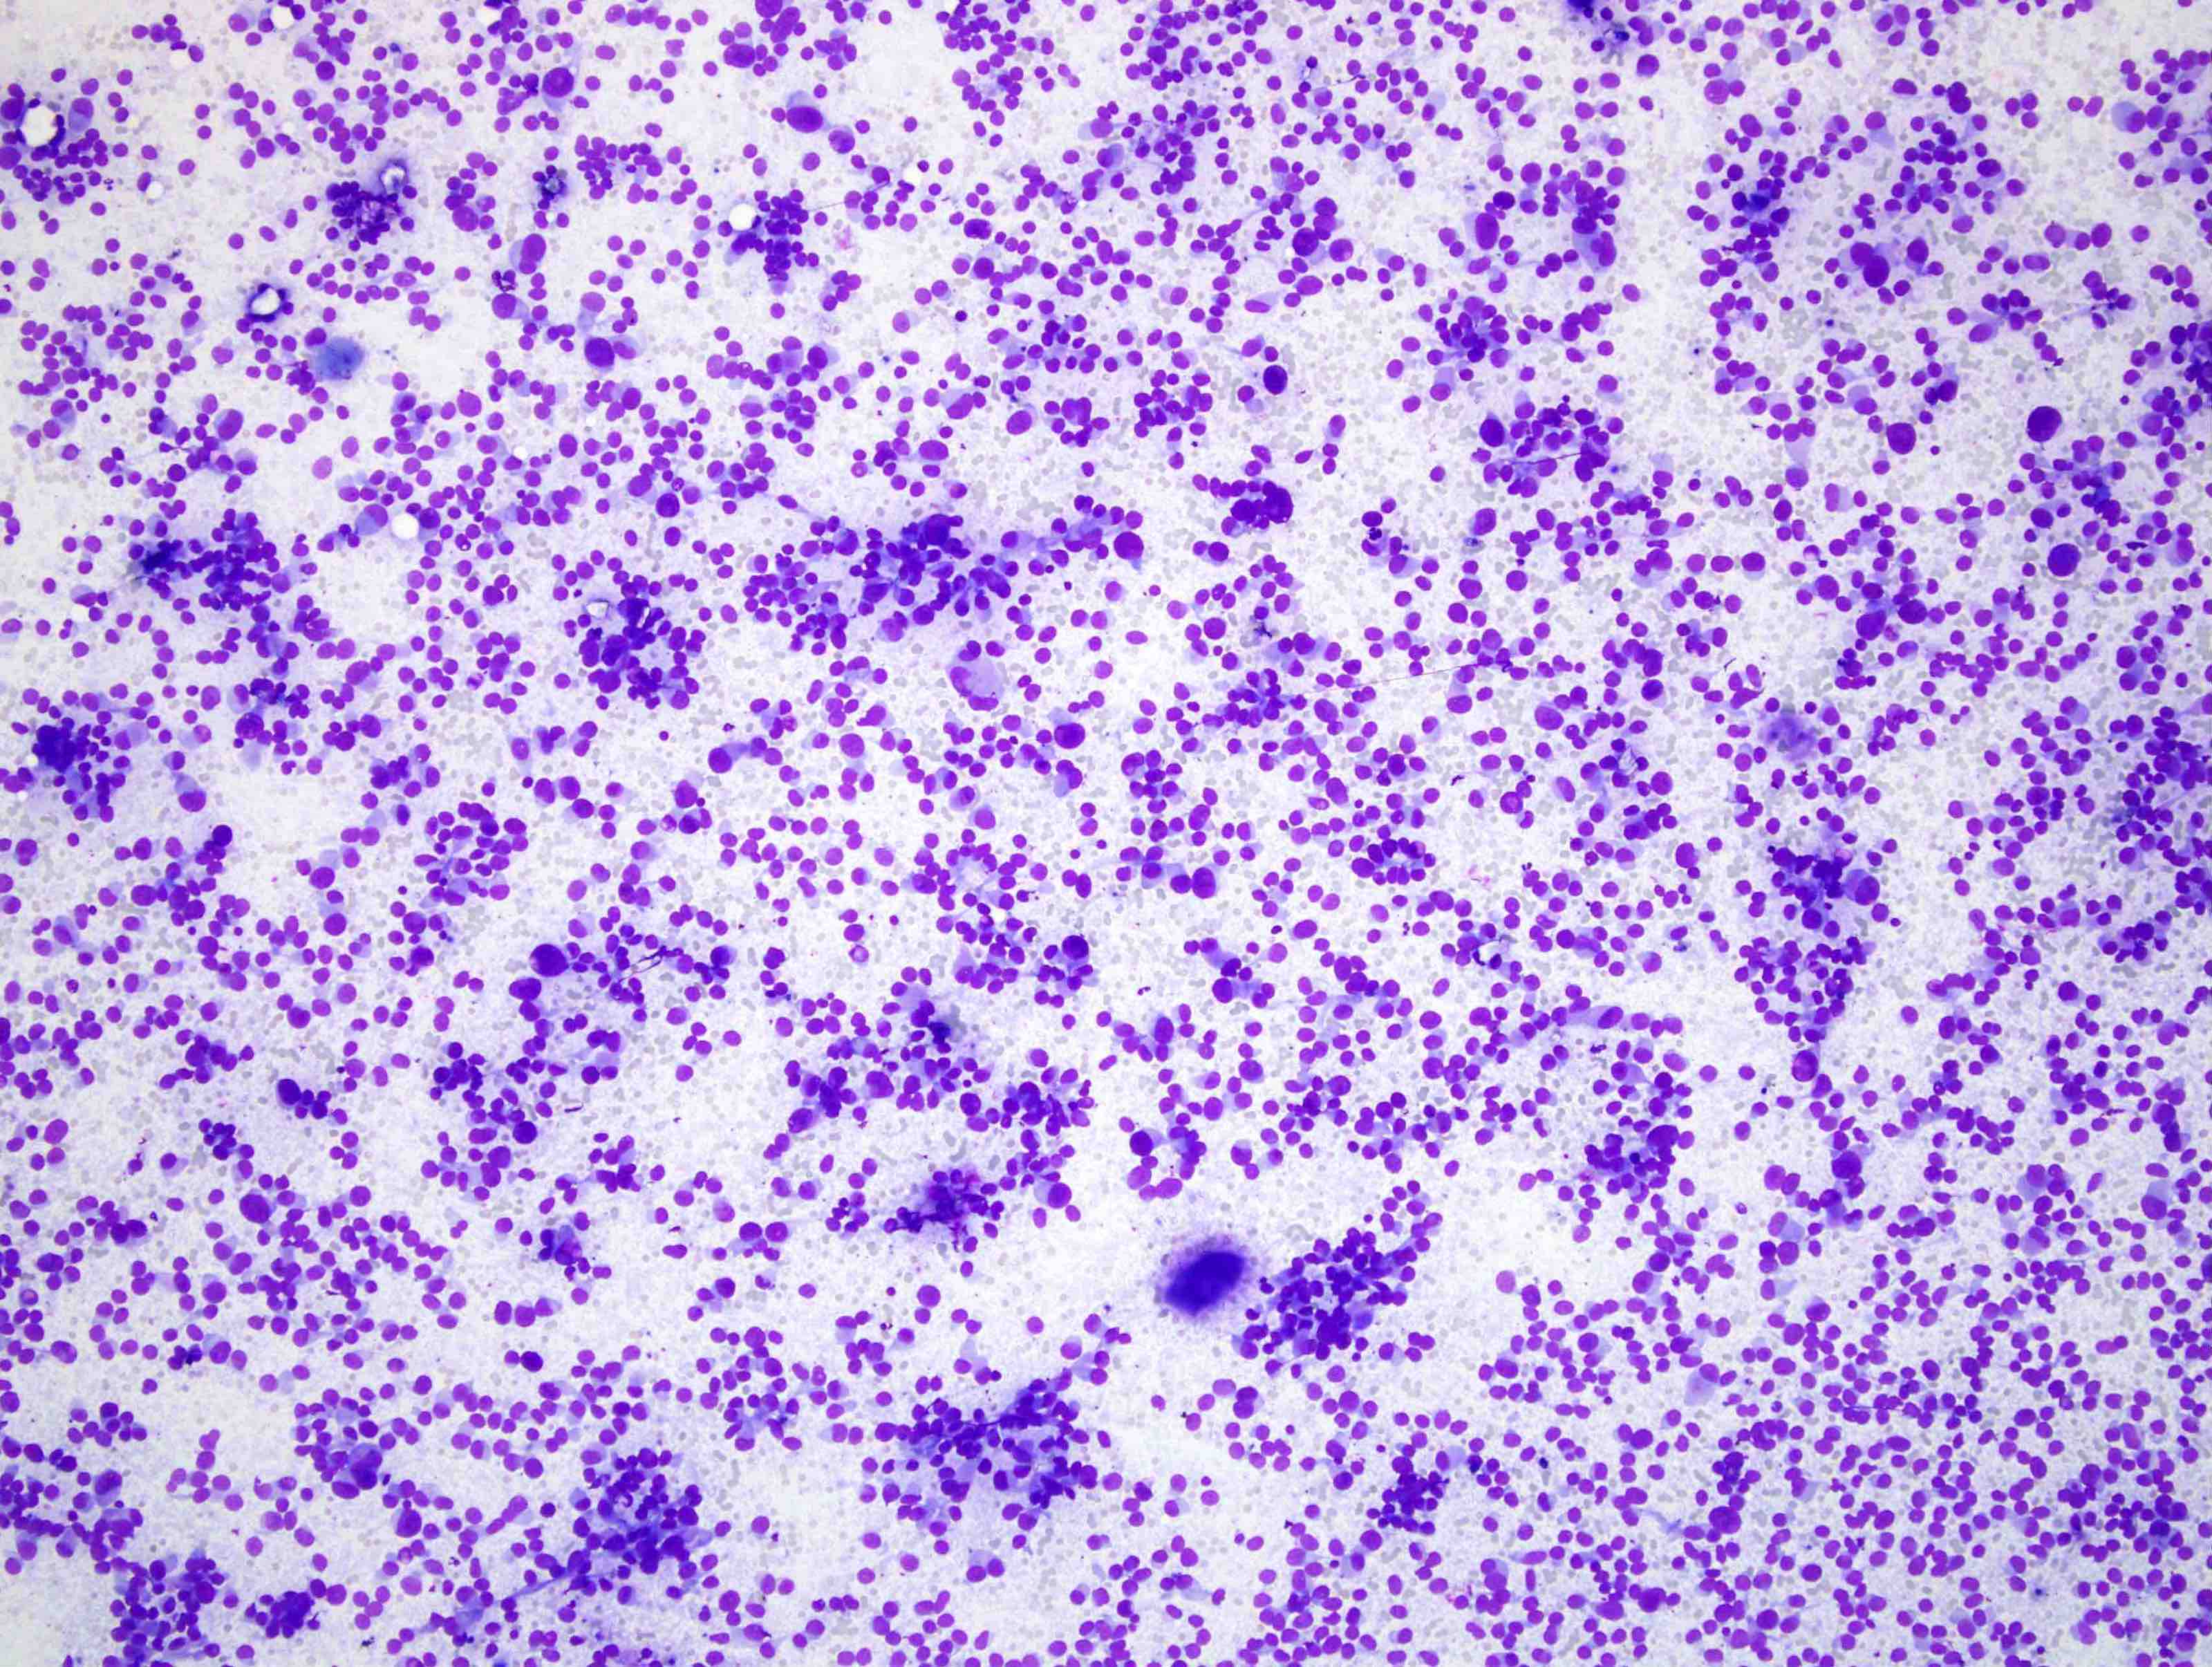

Cytology description

- Cellular specimen with round, ovoid, plasmacytoid or spindle cells singly or in small cluster; cells have abundant cytoplasm and eccentric nuclei; chromatin has salt and pepper appearance

- May have pink azurophilic granules and intranuclear pseudoinclusions; amyloid present occasionally (Am J Clin Pathol 1984;82:552)

- Paraganglioma-like variant:

- Predominantly ovoid to spindled epithelial cells in cohesive three dimensional clusters with sharp margins, rare isolated individual cells, no background colloid or amyloid

- Tumor cells have inconspicuous cytoplasm, significant nuclear atypia with occasional bizarre or binucleated cells, coarse and granular nuclear chromatin with occasional grooves and intranuclear inclusions (Cytopathology 2009;20:188)

Cytology images

Contributed by Ayana Suzuki, C.T. and Shuanzeng Wei, M.D., Ph.D.